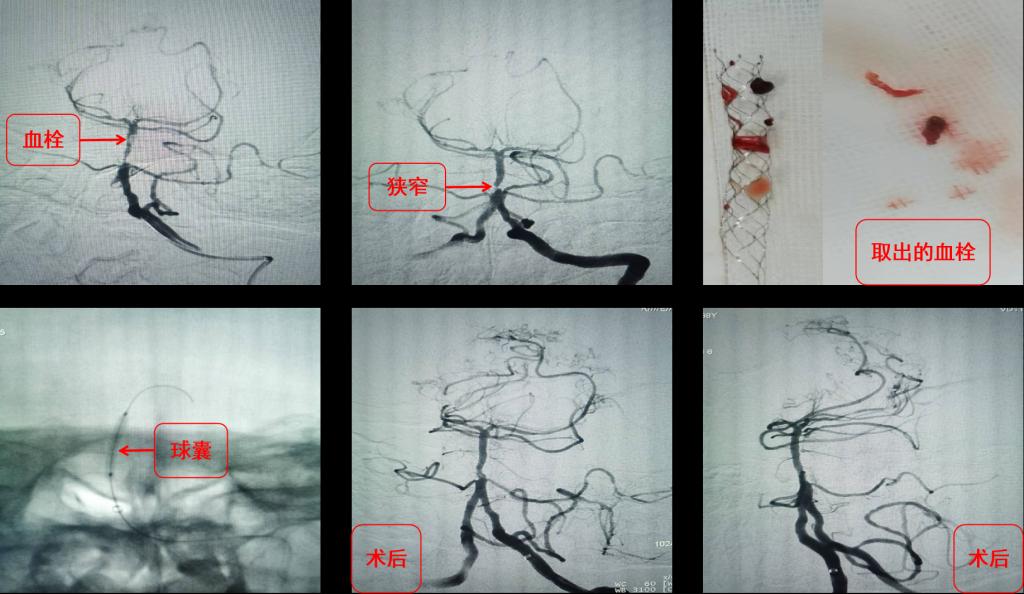

神经内科介入团队完成高难度无残端椎动脉长节段慢性闭塞再通

近日,神经内科完成多例椎动脉颅外段长段慢性闭塞再通术,使神经介入手术水平更上台阶。 患者拜某,男,65岁,因反复头晕、晕厥1年,加重10天入院,既往5年前因心肌梗死在外院冠脉植入5枚支架。本次发病后当地医院发现患者脑后部的主干动脉—...